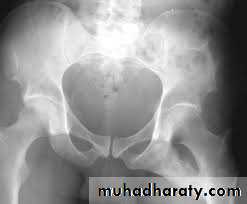

Radiological examination

two questions must be answered.Is there a fracture?

Is it displaced ?:Radiological classification

GRADE 1

:the femoral head is in its normal position or tilted into valgus and impacted on the femoral stump.GRADE 2

The femoral head is normally placed and the fracture line may be difficult to diagnosed

GRADE 3

The femoral head tilted out of position and the trabecular marking are not in line with those of innominate bone.GRADE 4

The femoral head trabeculae are normally aligned with those of innominate bone.